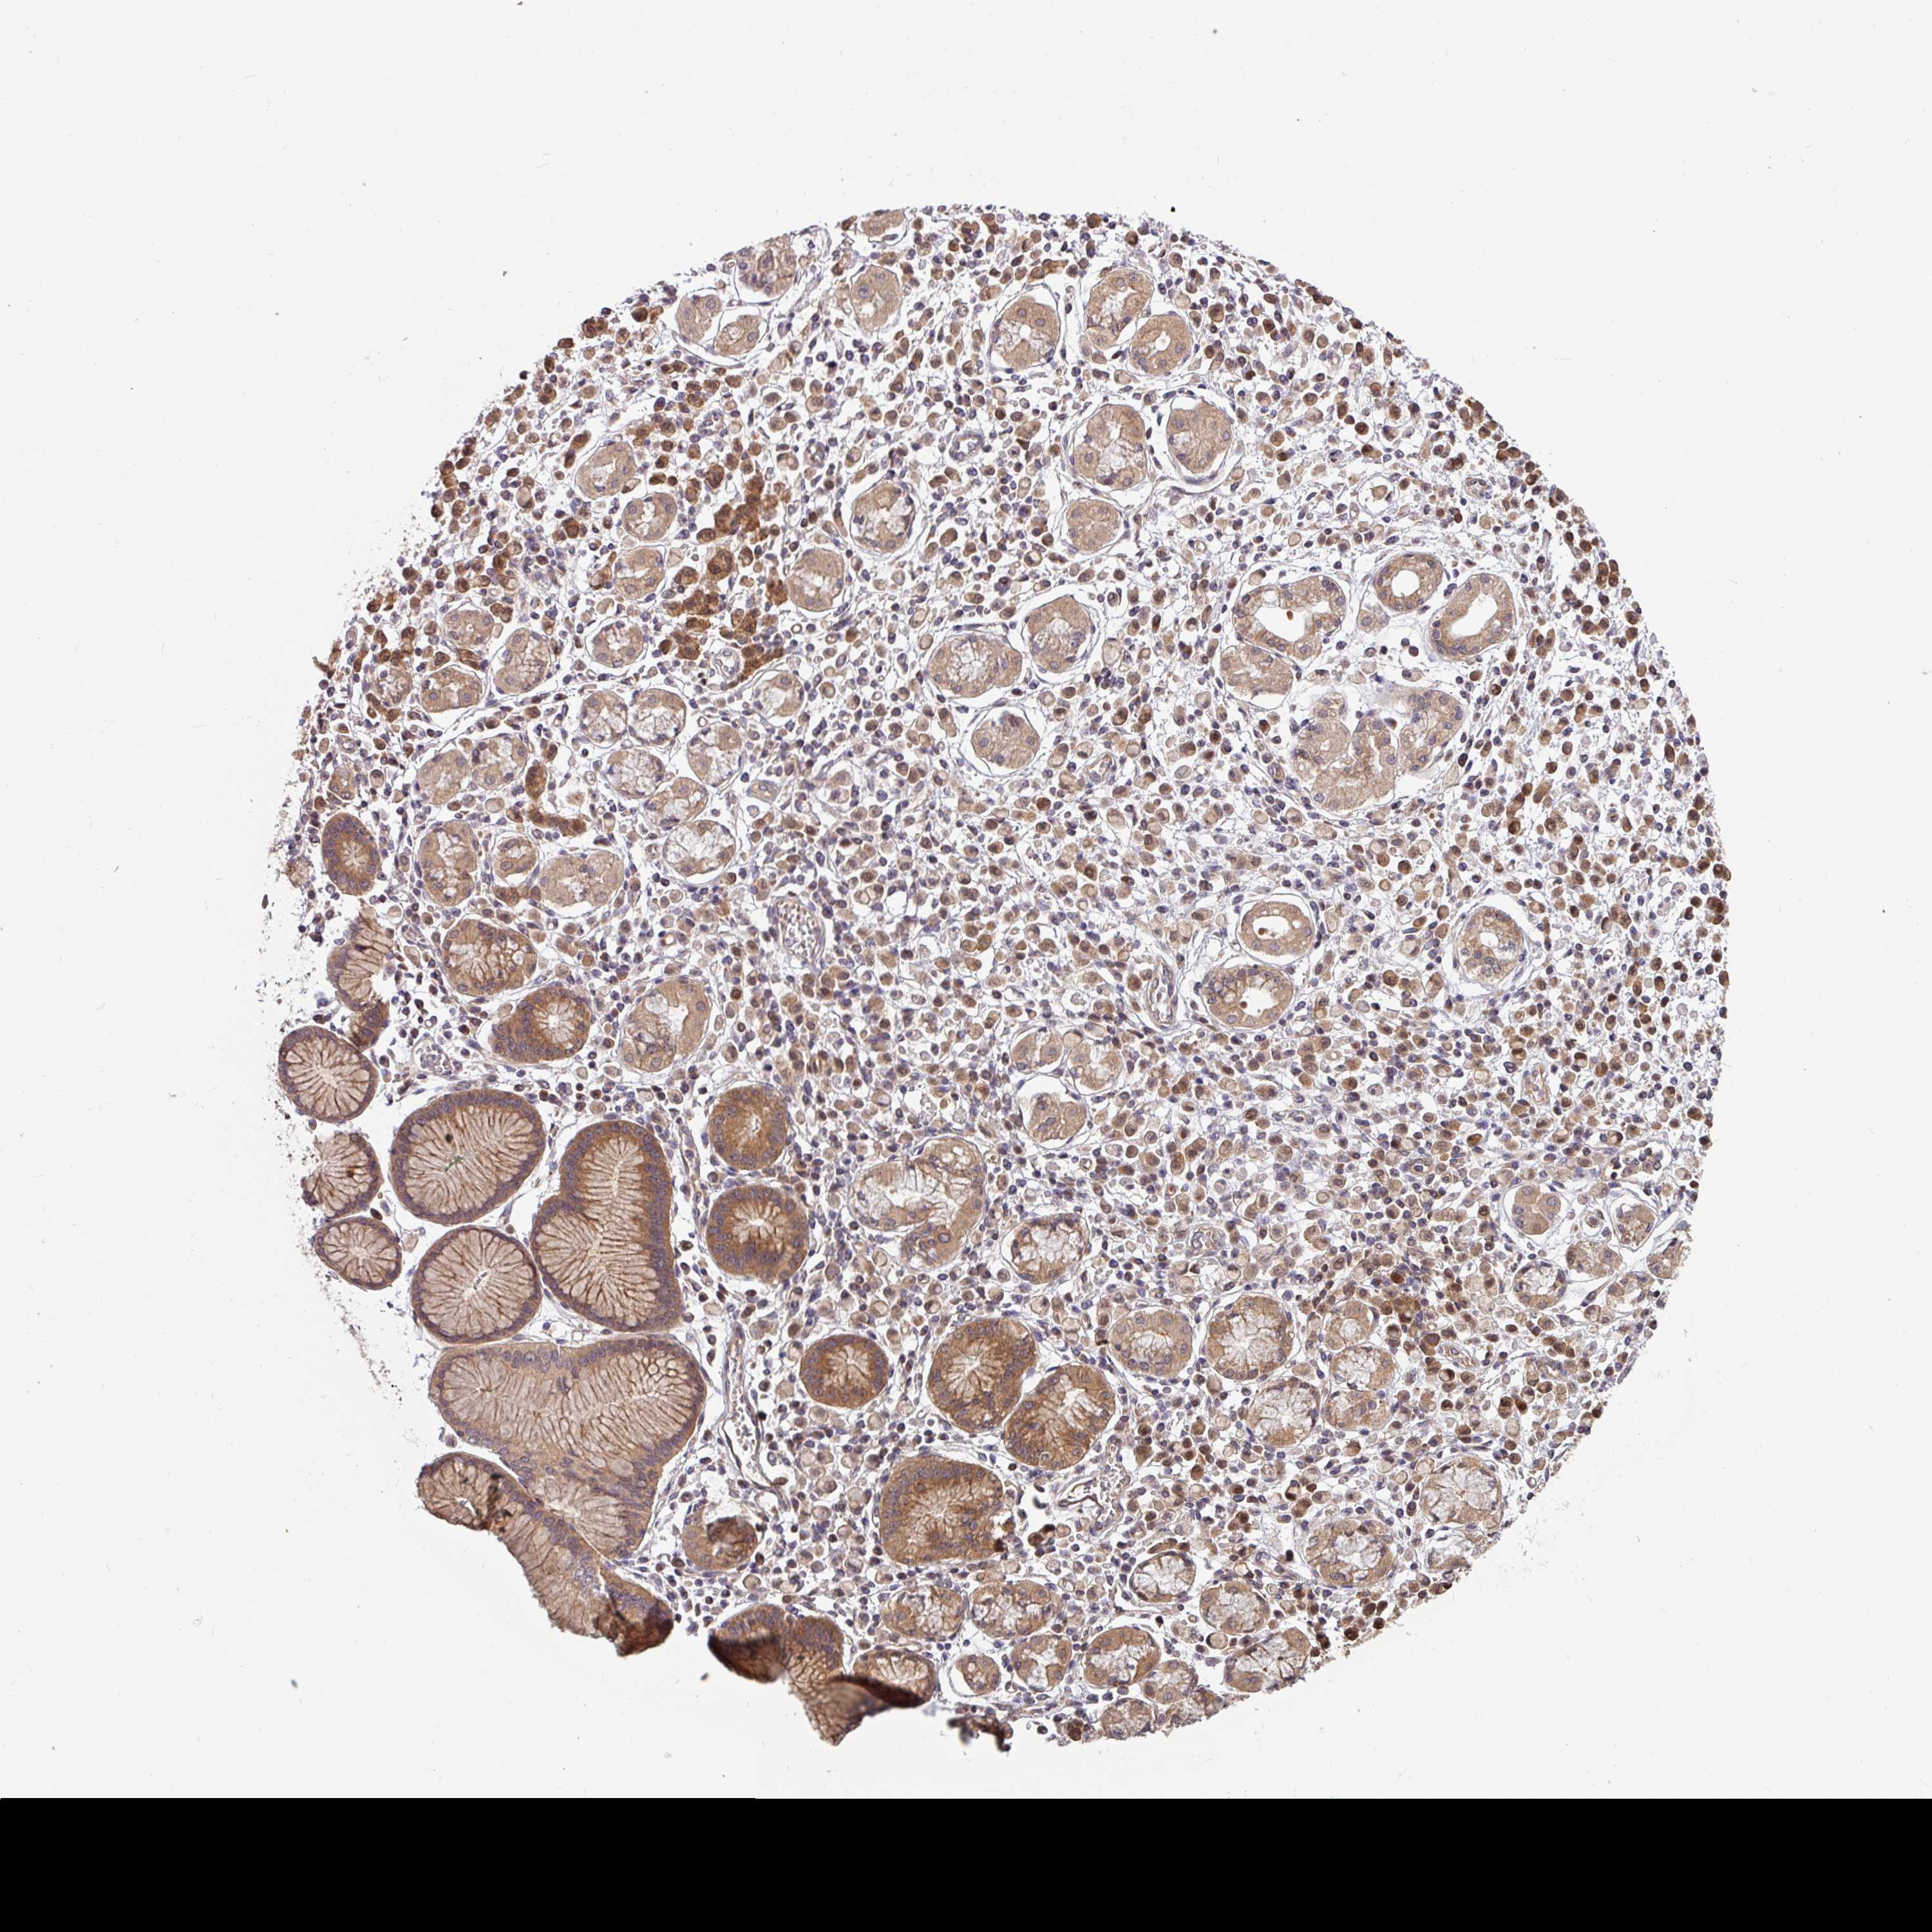

STOMACH CANCER - Protein expressioni

A mouse-over function shows sample information and annotation data. Click on an image to view it in a full screen mode. Samples can be filtered based on level of antibody staining by selecting one or several of the following categories: high, medium, low and not detected. The assay and annotation is described here.

Note that samples used for immunohistochemistry by the Human Protein Atlas do not correspond to samples in the TCGA dataset.

Antibody stainingi

Antibody staining in the annotated cell types in the current human tissue is reported as not detected, low, medium, or high, based on conventional immunohistochemistry profiling in selected tissues. This score is based on the combination of the staining intensity and fraction of stained cells.

Each image is clickable and will lead to virtual microscopy that enables deeper exploration of all samples and also displays staining intensity scores, fraction scores and subcellular localization as well as patient and tissue information for each sample.

Antibody HPA049911

Antibody CAB010161

Staining

High

Medium

Low

Not detected

Intensity

Strong

Moderate

Weak

Negative

Quantity

>75%

75%-25%

<25%

None

Location

Nuclear

Cytoplasmic/membranous

Cytoplasmic/membranous,nuclear

Adenocarcinoma, NOS